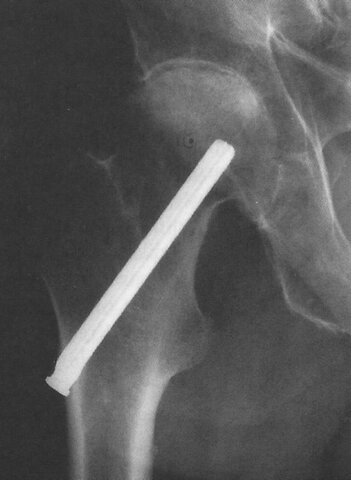

Marius Smith-Petersen desarrolla un dispositivo de vidrio destinado a la aplicación en prótesis parciales de cadera y clavos para la fijación de huesos

Materiales porosos

Se usan materiales porosos para el crecimiento del hueso alrededor del implante y se mejoran las técnicas quirúrgicas